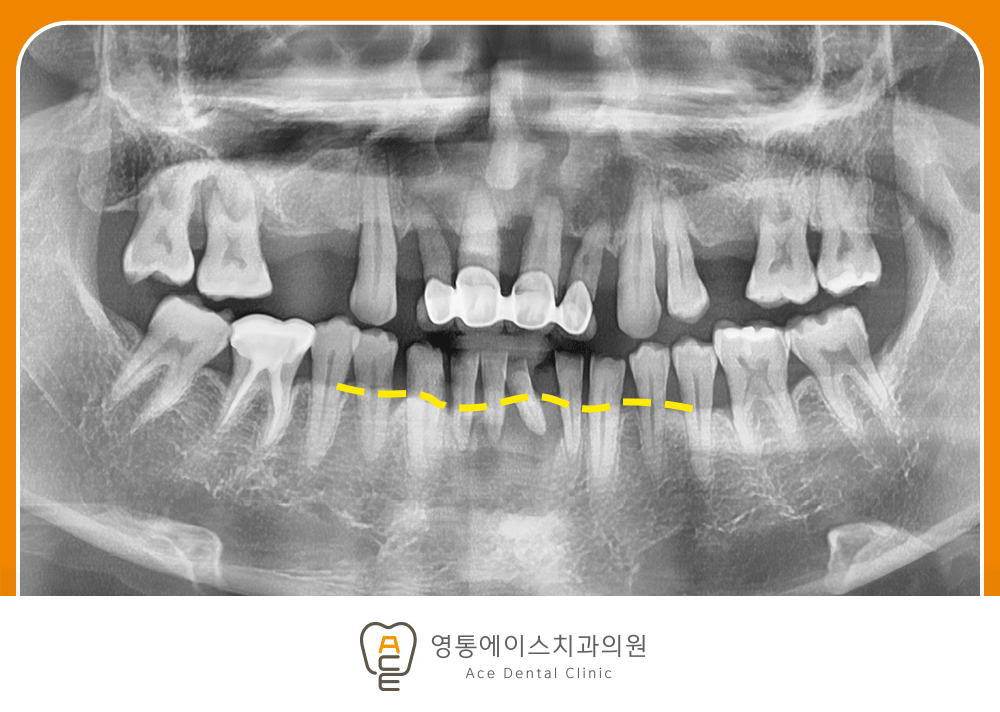

치료 전 사진 / 2024. 12. 09

잇몸 질환으로 인해 치아를 발치하게 된 경우에는 단순히 빠진 치아만 다시 채우는 것이 아니라, 잇몸과 잇몸뼈의 상태를 함께 확인하는 과정이 중요합니다.

앞니 주변 잇몸뼈가 염증으로 인해 많이 손상된 상태라면 임플란트를 바로 식립하기 어려울 수 있습니다.

이 경우에는 염증을 먼저 제거하고, 부족한 뼈를 보강하기 위한 뼈이식이 필요할 수 있습니다.

잇몸뼈가 충분히 회복되어야 임플란트가 안정적으로 자리 잡을 수 있기 때문입니다.